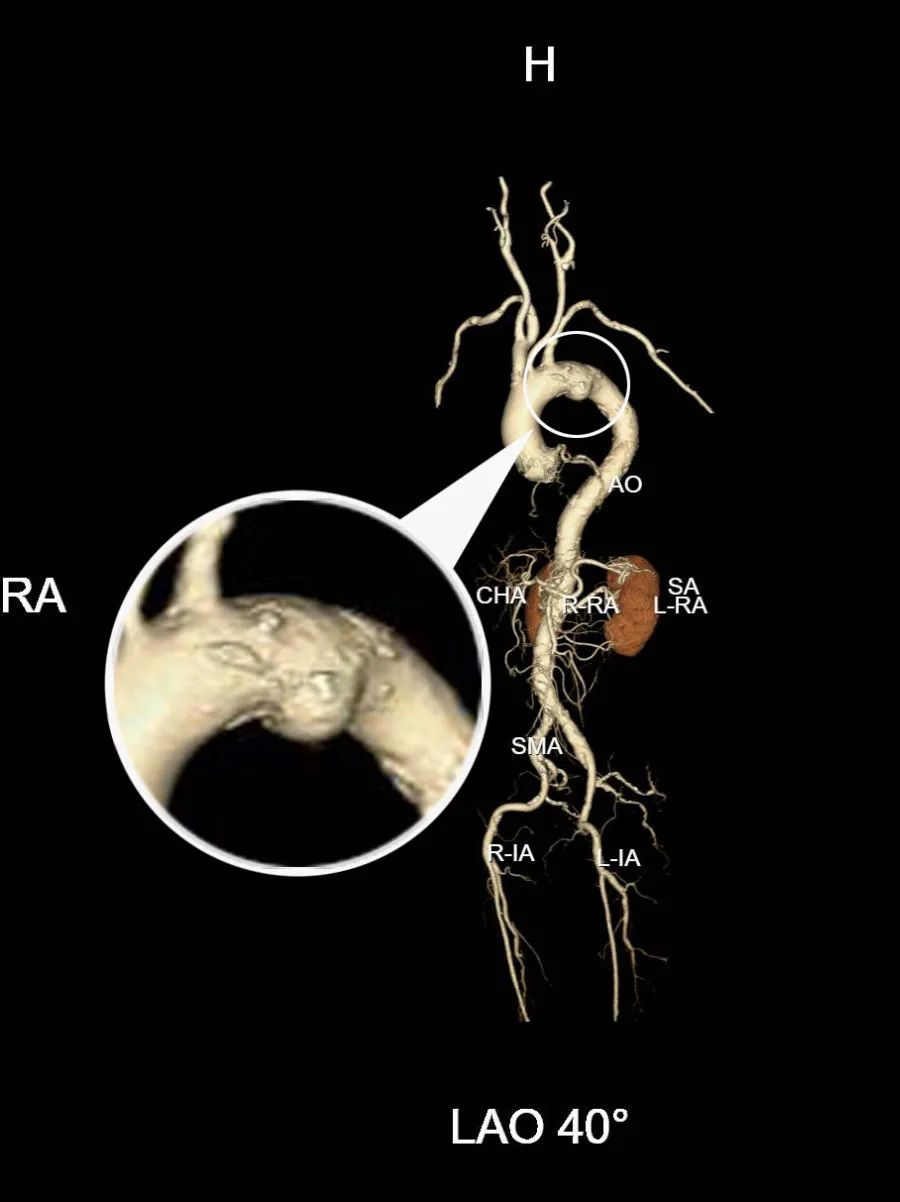

近日,吴爷爷因为慢性支气管炎急性发作,到奉城医院呼吸科住院治疗,住院期间进行CT检查,CT报告显示:主动脉弓部动脉瘤可能?

夏向红医生收到报告后,马上联系血管外科宋菊民主任进行会诊,完善肺动脉CTA(CT血管造影)。

复查报告显示主动脉弓动脉瘤伴血栓形成可能

手术在刘光主任的指导下,由宋菊民、张荣、郭信医生在全麻下进行,历经1小时30分钟,仅在患者右股动脉有一个穿刺点,左手臂留有一个微小切口。

置入支架,危机解除